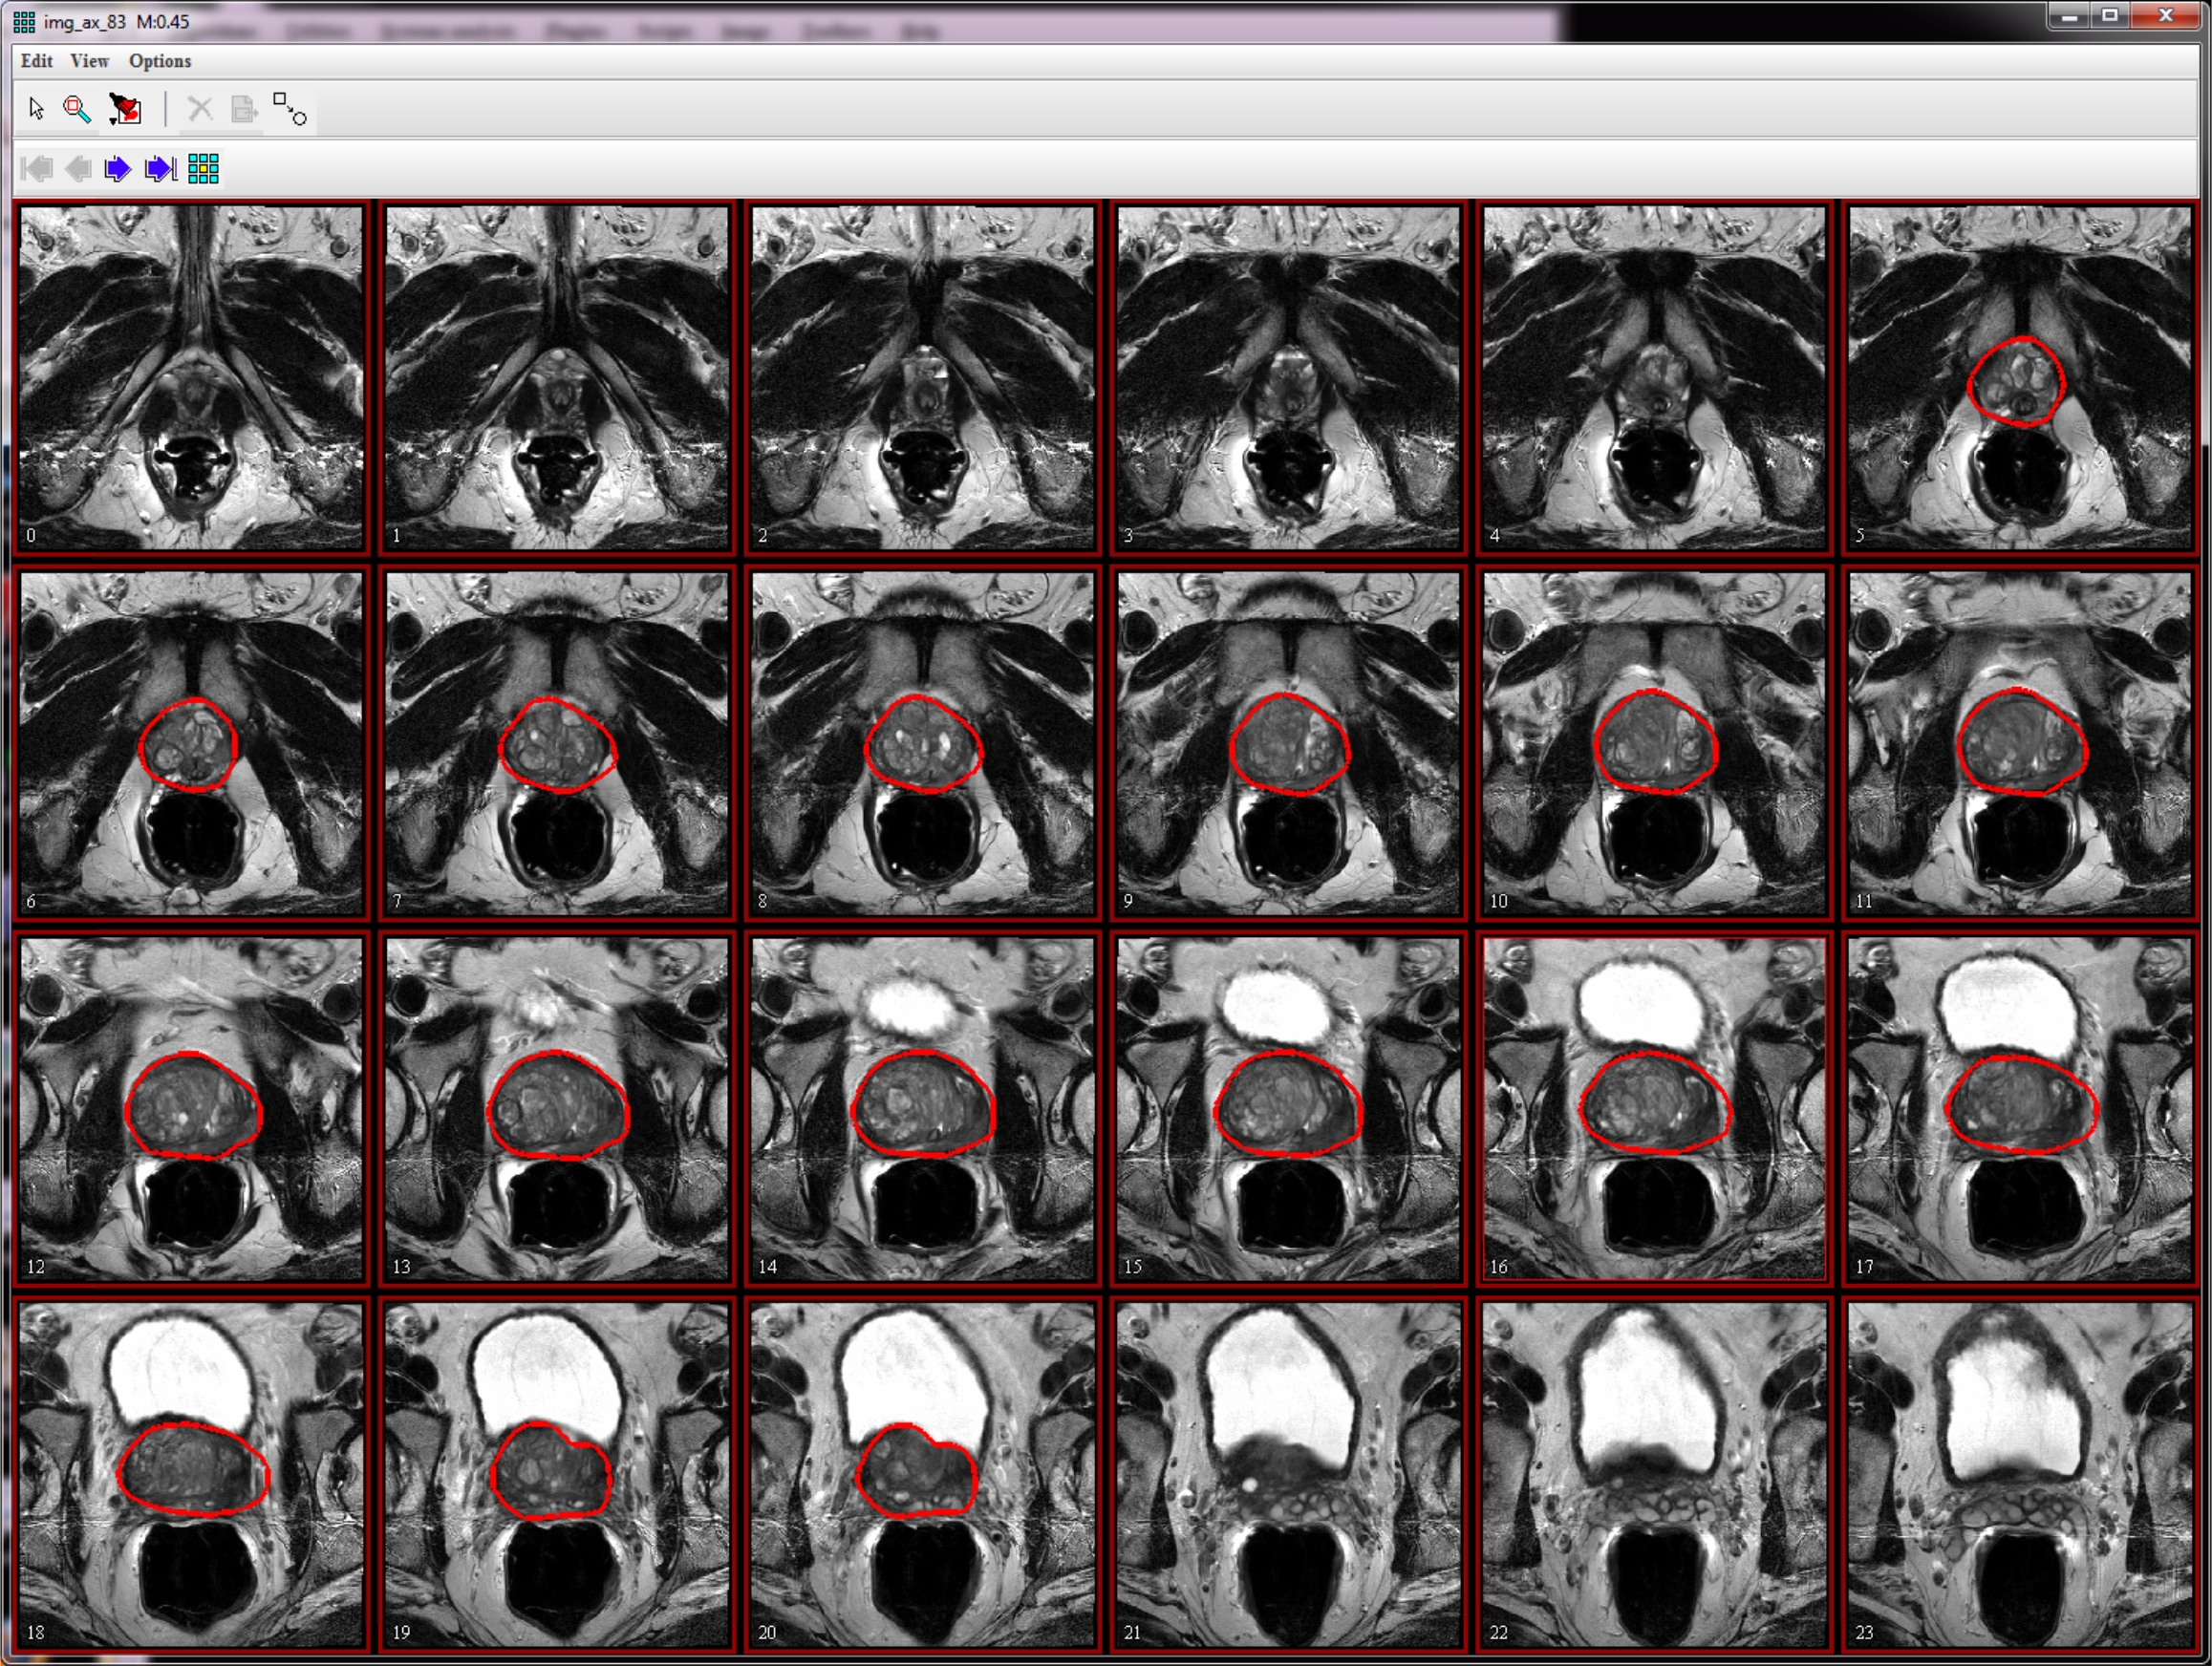

To open an axial image, use File > Open image (A) from disk menu. If you are using the sample image dataset provided, open the img_ax_83.xml file.

To delineate prostate VOIs, use the Polygon/Polyline VOI tool

from the MIPAV toolbar.

For example, if you work with the sample image dataset: